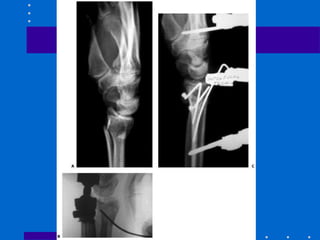

Fixação interna - Placa volar

• Devido às complicações antes citadas,

muitos autores têm indicado fixação das

fraturas dorsalmente deslocadas através de

abordagem palmar - não dá apoio contra

dorsal deslocamento

• cuidar último parafuso para não penetrar

articulação

• Não pode haver cominuição dorsal

• Abordagens

# entre flexor radial do carpo e artéria radial

– melhor exposição para coluna

radial(estilóide)

#entre flexores e feixe ulnar – acessa coluna

intemediária(fossa lunar)